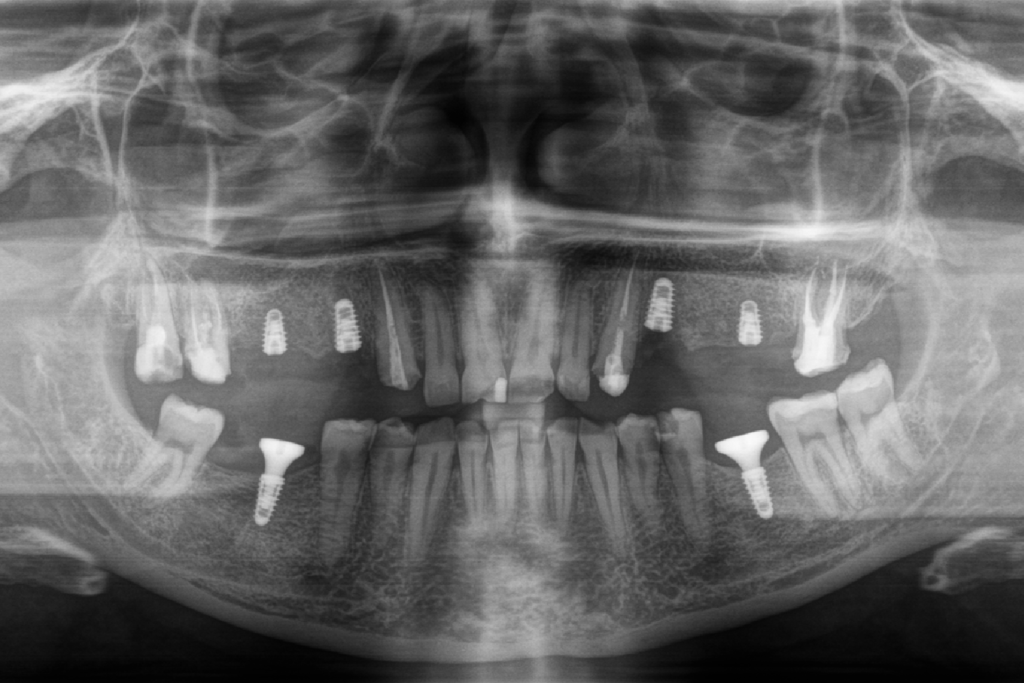

Лікар видалив залишки зубних коренів на верхній та нижній щелепі, одномоментно встановив у лунки шість зубних імплантів Straumann BLX та шість формувачів ясен. Операція тривала півтори години.